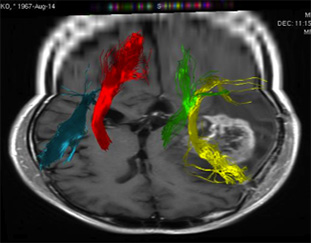

トラクトグラフィー Tractography

脳内の神経線維を詳細に調べ、脳腫瘍と重要な神経線維がどのような関係にあるのかを調べ、手術の時にこれらが損傷しないような手術プランを計画します。

(右図)赤色は右の運動神経線維、緑は左の運動神経線維。黄色は言語機能の連絡をする神経線維を示しています。